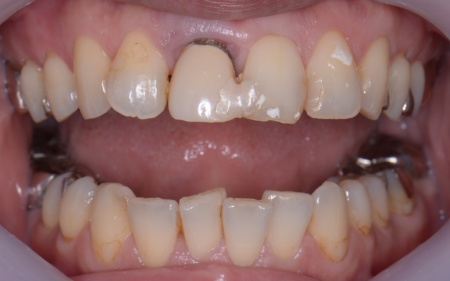

50代女性 歯根が折れた歯を抜いてインプラント治療と前歯の部分矯正を行った症例

「右上前歯に装着されていた差し歯が取れてしまった」とご相談いただきました。

拝見したところ、右上前歯(中切歯)は歯根が折れて温存が難しく、抜歯が必要な状態でした。

また上下前歯はやや歯並びの乱れがあり、これによって噛み合わせのバランスが崩れて、特定の歯に過度な力がかかっていたことが、歯根が折れる原因になったと考えられます。

画像をクリックすると拡大・詳細コメントを確認いただけます

インプラントを埋入しました。

骨と歯肉の移植を行いました。

部分矯正中です。